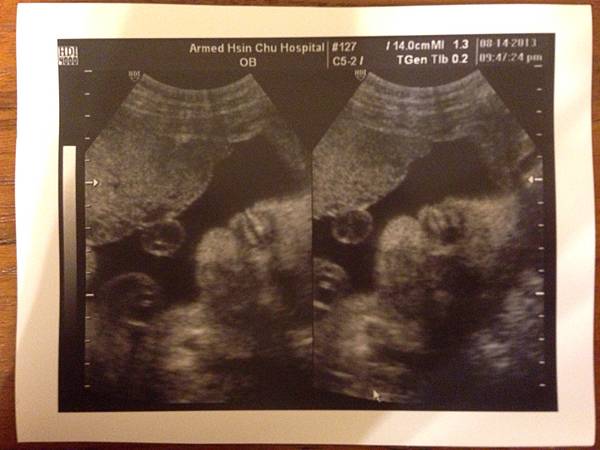

(20130814) 57.3kg "產檢時 57.6kg: 52.4(12w)+0.7(17w)+1.7kg(21w)+ 1.4(25w) + 1.4(29W)"

一開超音波, 我還沒回神, (根本連醫生在講哪裡都還看不出來)

翁醫生立馬就說, "陳小皮是個雙眼皮呦~ 生出來後要記得確認一下!~"

嗚吼~ 回家後, 看了很久, 終於看懂醫生在講哪裡了! (是說陳先生原本也跟我一樣看不出來...)

有沒有, 整個就是大正面, 眼睛有沒有超級大的!!!~

而且本月份陳小皮長很快, 一下下就衝到 1650g 了. 大約是 30w 左右的大小.

是的頭大(31w), 肚子還好(30w), 腳一般(29w) 的孩子 >"<

不過不好的消息是... 陳小皮臍帶繞頸啦...